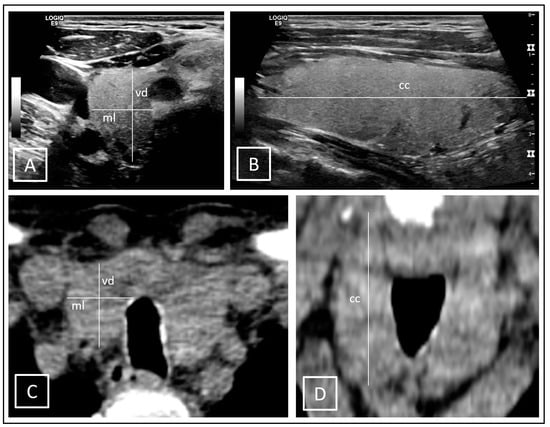

Two different methods were used to measure the thyroid volumes. ConUS data were evaluated via the ellipsoid model (conUS-EM): V = (4/3) * π * (largest cranial-caudal diameter/2) * (largest anterior-posterior diameter/2) * (orthograde medial-lateral diameter/2) [24]. Volume determination of the stitched 3D-US data sets were performed by multiple manually drawn segmental contouring applications (MC) in transverse plane in PMOD software according to the organ boarders (3DsnUS-MC, 3DmsUS-MC). The same method was also used to measure the thyroid volumes on I-124-PET/CT scans in Syngo.via software (PET/CT-MC), which defined the reference standard values. To avoid prejudiced biases, determination of the reference was performed only after the measurements of the thyroid volumes on the several US data sets. For further comparative analyses, the CT scans alone were additionally evaluated in Syngo.via software using both the MC and EM methods (CT-EM, CT-MC). ConUS-EM and CT-EM applications are demonstrated in Figure 4.

Figure 4.

Ellipsoid model (EM) exemplarily demonstrated on a right thyroid lobe on conUS images in transverse (A) and sagittal (B) planes as well as on CT images in transverse (C) and coronal (D) planes; diameters: vd = ventral-dorsal, ml = medial-lateral, cc = cranial-caudal.